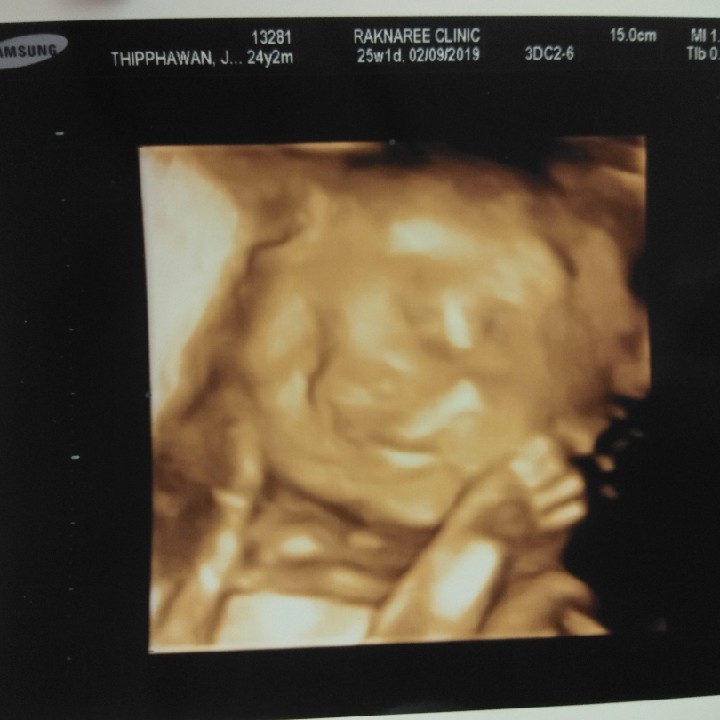

ผู้ ญ ค่ะ 25 Week

25w2d ลูกสาวจ้า